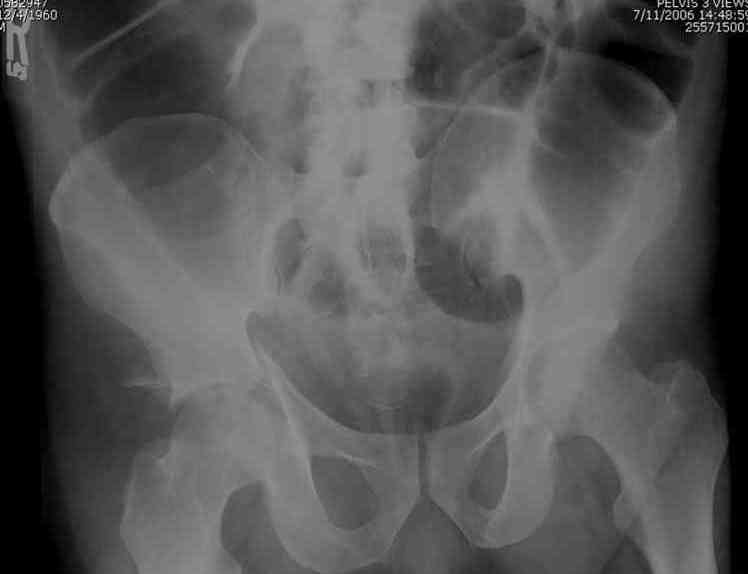

45 yo male in MVA, only other injury=small subarrachnoid bleed (neurologically fine, GCS never <14), with this transverse & associated posterior wall fx-dislocation 7/7

In skeletal traction thru distal femoral pin 40 lbs with decent reduction - except for the free fragments in the hip joint. ORIF planned for post-injury day 11.

Biggest problem appears to be impaction & comminution of the posterior wall fx site - you've left out some CT cuts. This is not just fragments in joint. It may leave a deficient area, &/or block satisfactory posterior wall reduction.